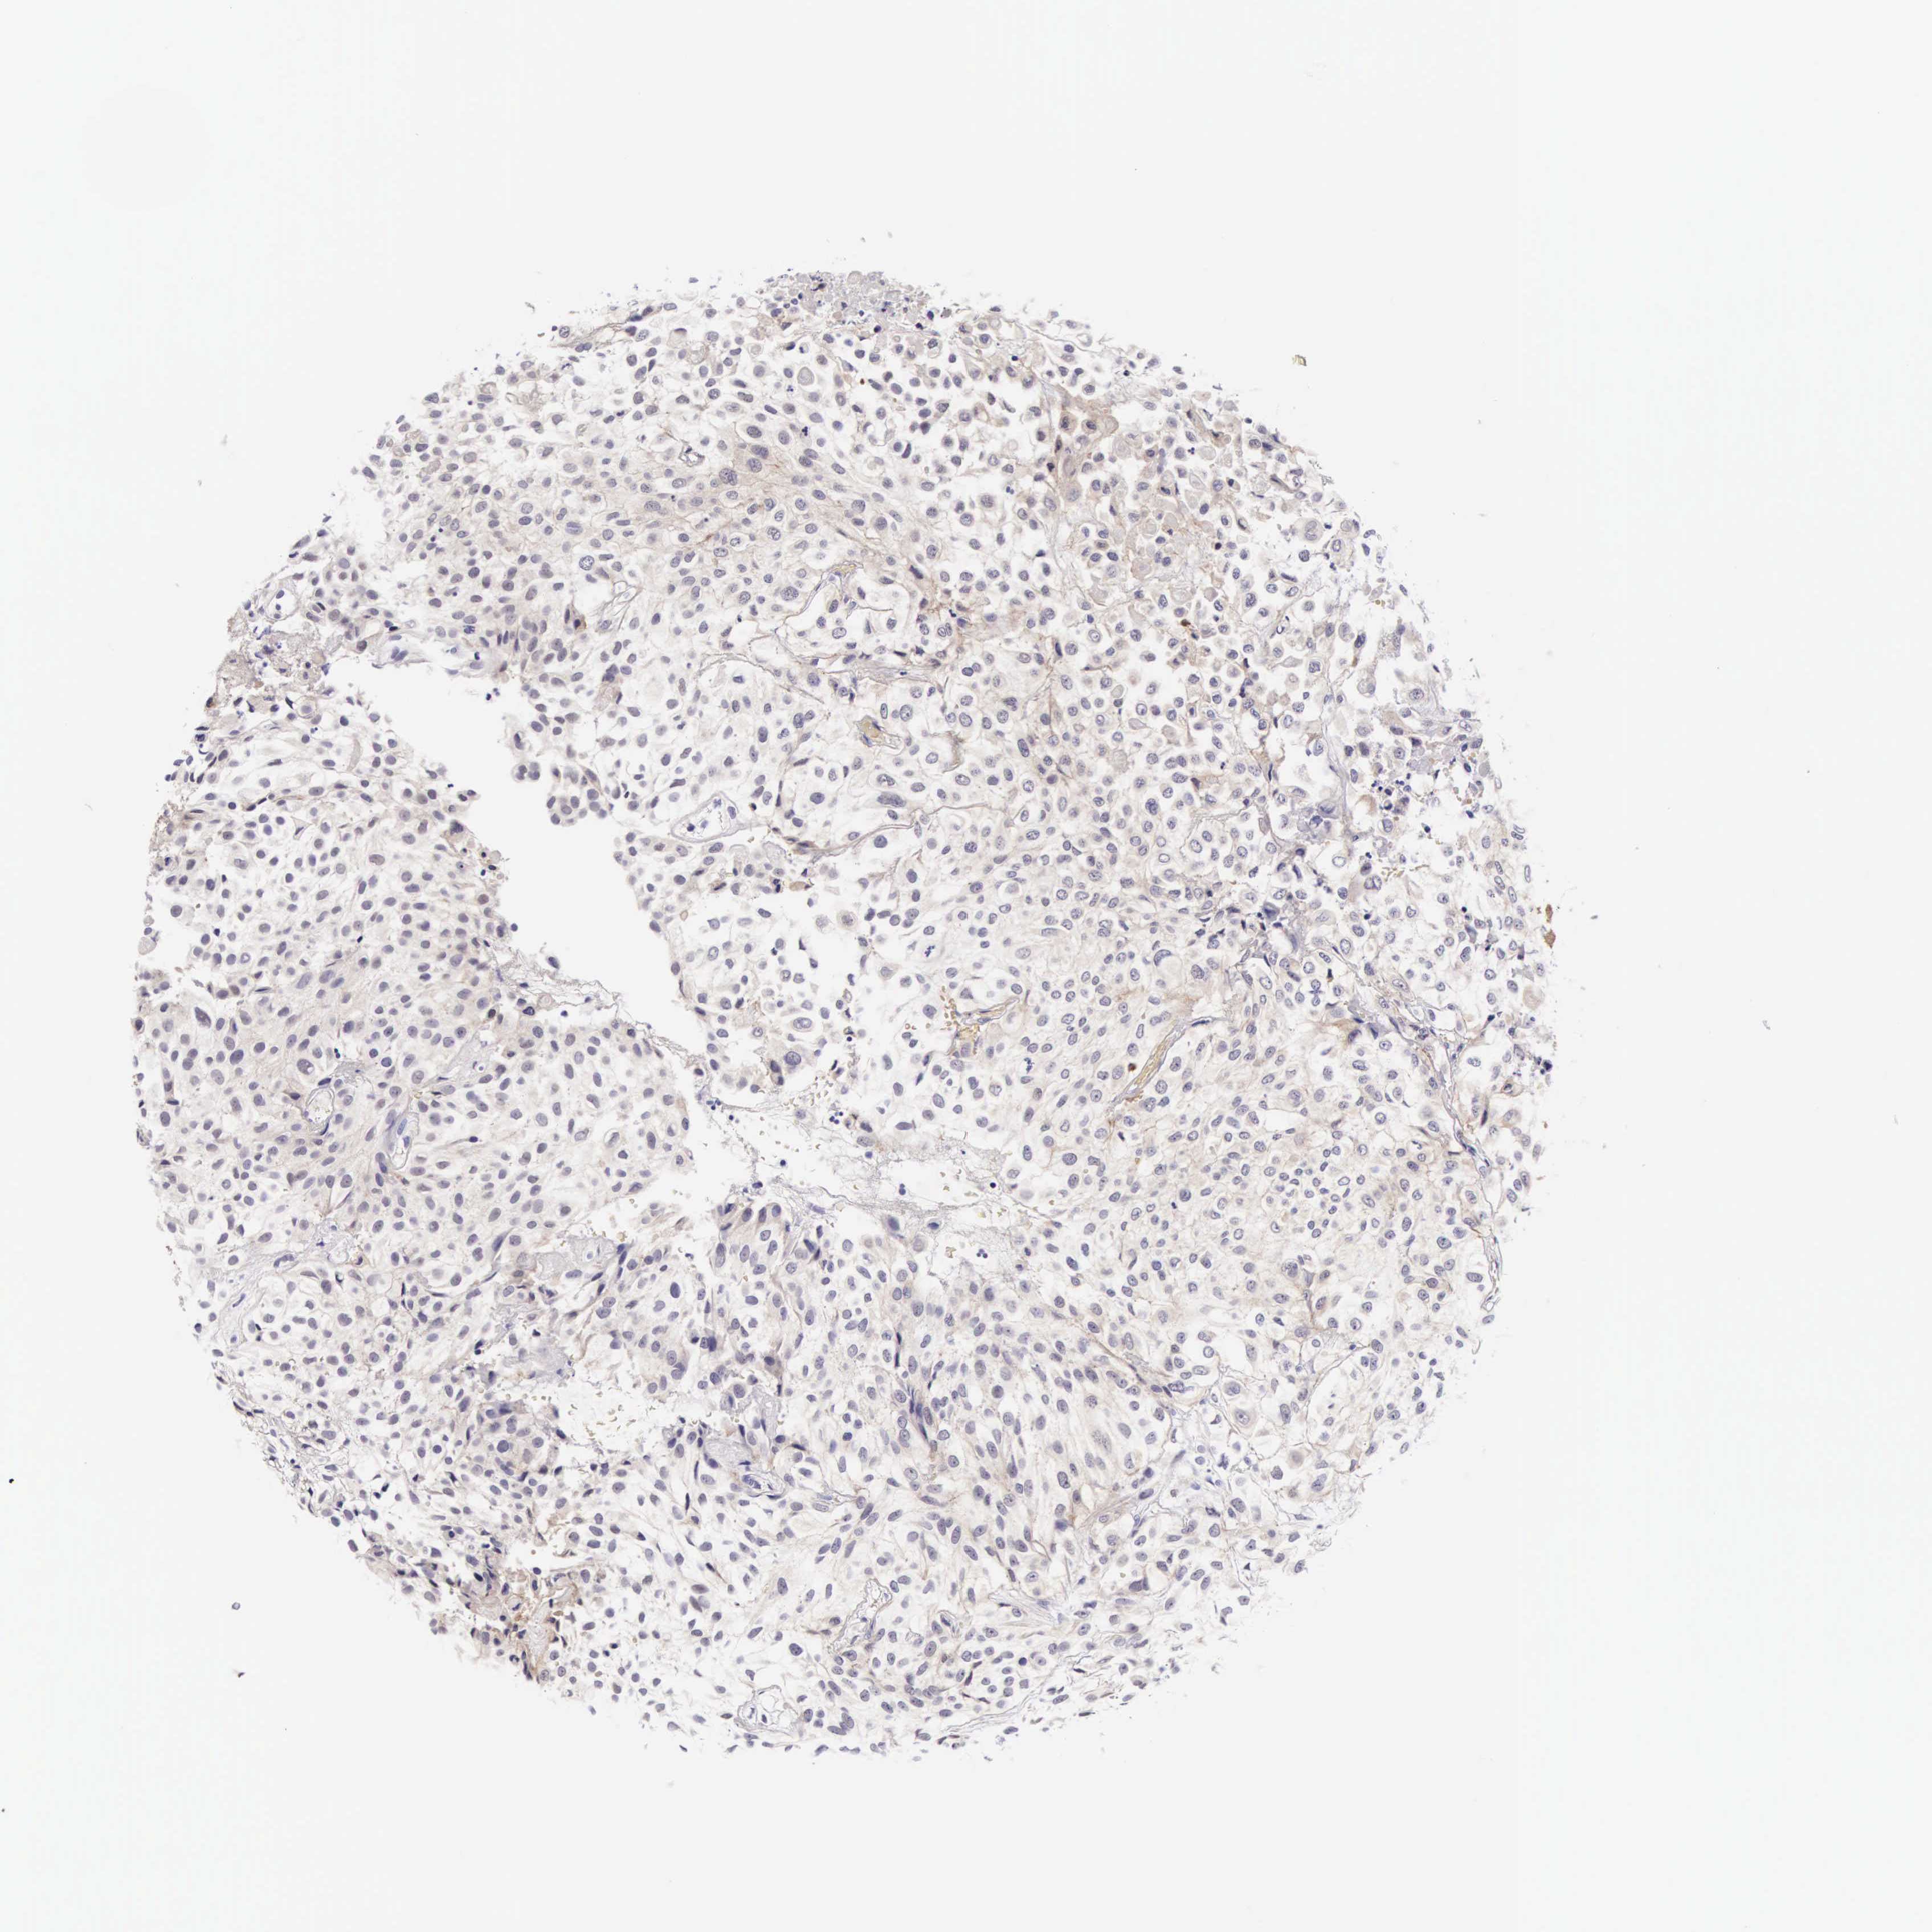

UROTHELIAL CANCER - Protein expressioni

A mouse-over function shows sample information and annotation data. Click on an image to view it in a full screen mode. Samples can be filtered based on level of antibody staining by selecting one or several of the following categories: high, medium, low and not detected. The assay and annotation is described here.

Note that samples used for immunohistochemistry by the Human Protein Atlas do not correspond to samples in the TCGA dataset.

Antibody stainingi

Antibody staining in the annotated cell types in the current human tissue is reported as not detected, low, medium, or high, based on conventional immunohistochemistry profiling in selected tissues. This score is based on the combination of the staining intensity and fraction of stained cells.

Each image is clickable and will lead to virtual microscopy that enables deeper exploration of all samples and also displays staining intensity scores, fraction scores and subcellular localization as well as patient and tissue information for each sample.

Antibody HPA000647

Staining

High

Medium

Low

Not detected

Intensity

Strong

Moderate

Weak

Negative

Quantity

>75%

75%-25%

<25%

None

Location

Nuclear

Cytoplasmic/membranous

Cytoplasmic/membranous,nuclear

Urothelial carcinoma, High grade

Urothelial carcinoma, Low grade